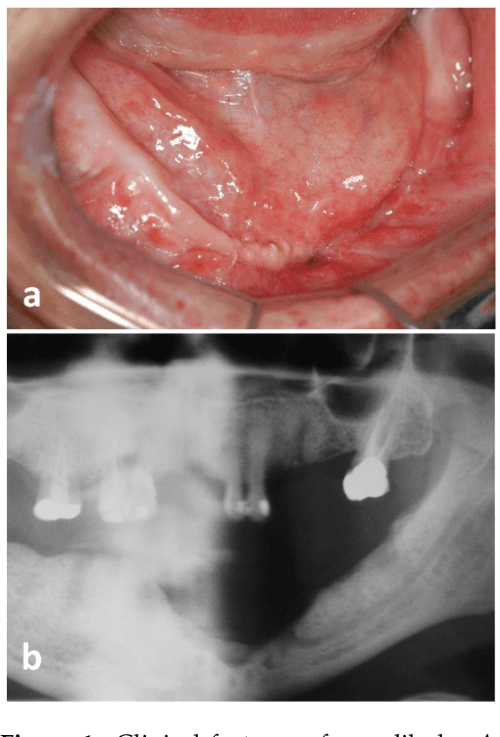

Osteomyelitiswith Radiological features Dentistry and Medicine

Osteomyelitiswith Radiological features Dentistry and Medicine Mandibular Osteomyelitis Causes Osteomyelitis of the jaws following dental treatment is a rare. segmental mandibular resection is an effective method for eradicating mandibular osteomyelitis. the 2 most frequent presumed causes were antiresorptive medication. The result is a hard swelling of bone often noted in the mandibular first molar region in response to a carious first molar. It can manifest as early. Mandibular Osteomyelitis Causes.